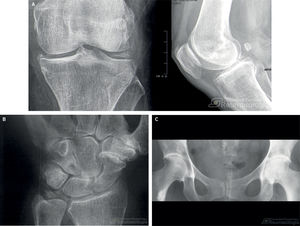

Lo que aportan las pruebas complementariasLas pruebas complementarias aportan información clave para el diagnóstico diferencial, aunque no siempre son necesarias de inicio. La radiografía simple suele ser la primera prueba y debe incluir proyecciones anteroposterior y lateral, preferiblemente en carga y de ambas rodillas. Si se pretende descartar fractura, es aceptable radiografiar solamente el lado afecto. La radiografía permite confirmar la presencia de artrosis de rodilla, mediante hallazgos como estrechamiento del espacio articular, esclerosis subcondral y osteofitos (fig. 3), además de ayudar a evaluar la severidad y guiar la decisión quirúrgica. No obstante, el diagnóstico de gonartrosis suele ser clínico en mayores de 45 años11, por lo que guías como la NICE (National Institute for Health and Care Excellence) recomiendan limitar la radiografía a las presentaciones atípicas, progresión rápida o sospecha de diagnósticos alternativos como enfermedad por depósito de pirofosfato cálcico o tumores. Ante sospecha de artritis por pirofosfato (pseudogota), es útil revisar radiografías previas de manos o sínfisis del pubis, que también son localizaciones típicas de condrocalcinosis (fig. 4).